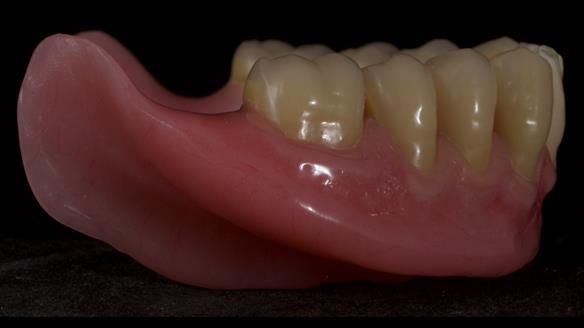

Welcome to Newsletter 83. This month I am sharing Sheila’s case — a very challenging but rewarding complete denture case. Sheila had flat ridges, a small mouth opening, a large tongue and had never been able to wear complete dentures of any kind. Everything was loose and sore. She felt embarrassed and looked older without dentures. She wanted a stable, comfortable result, and she wanted to avoid implants because she has taken bisphosphonates for more than five years.

In Sheila’s case, the Dr Abe shaped impression gave a more stable and comfortable result. Sheila preferred the shape produced by the Abe method, so that is the one we used for the registration rims, the trial denture and the final dentures. But making both impressions was worthwhile. It meant we had every option covered and could choose what worked best for her mouth.

I also want to give a BIG shout out to Rowan, my dental technician. His technical skills are extraordinary, and I could not do this level of work without him. His attention to detail and craftsmanship play a huge part in the success of cases like this.